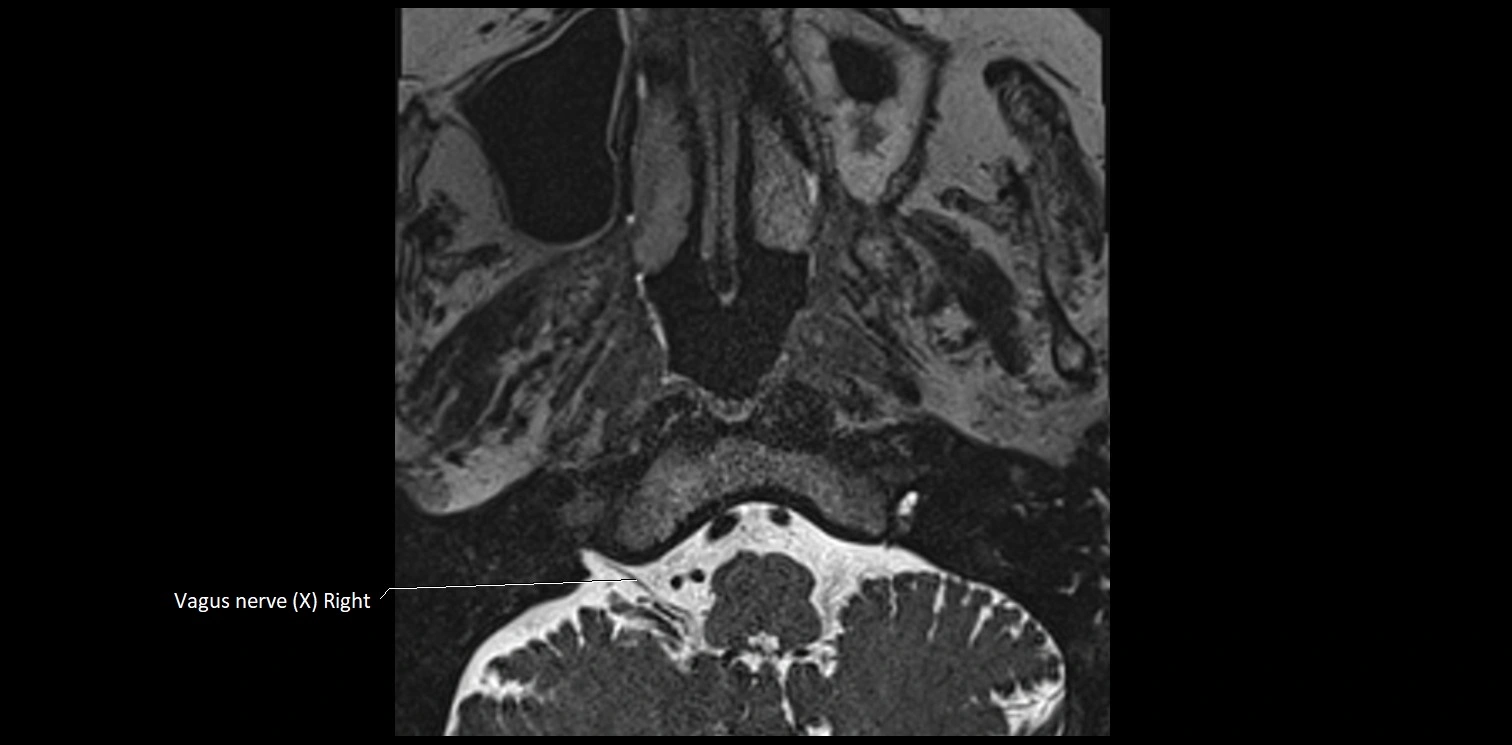

MRI Appearance

• The abducens nerve is a small, thin, linear structure

• Best visualized on high-resolution T2-weighted 3D MRI sequences (e.g., FIESTA or CISS)

• Seen as a hypointense (dark) line running from the brainstem at the pontomedullary junction, traversing the prepontine cistern, and entering Dorello’s canal under the petrosphenoidal ligament, then into the cavernous sinus, and finally the orbit

• May be challenging to visualize in standard MRI due to its small size

• Pathology may be inferred by absence, displacement, or enhancement of the nerve